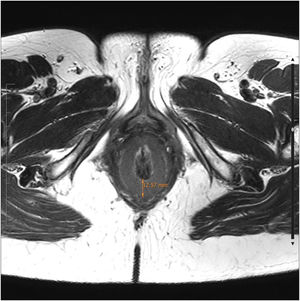

We present the case of a 53-year-old woman, whose medical history of interest only included cesarean section for the delivery of twins. She reported symptoms of proctalgia and difficulty passing stool over the past 3 years. On physical examination, she presented with pain during digital rectal examination and anal hypertonia, with no associated fissure. We performed endoanal ultrasound and requested a dynamic pelvic MRI, which showed homogeneous circumferential thickening of the IAS, in addition to tricompartmental pelvic floor descent during defecation, with no relaxation of the IAS. The patient did not improve with oral muscle relaxants, topical nifedipine, or local infiltration of botulinum toxin, and she is awaiting internal lateral sphincterotomy (Figs. 1 and 2).